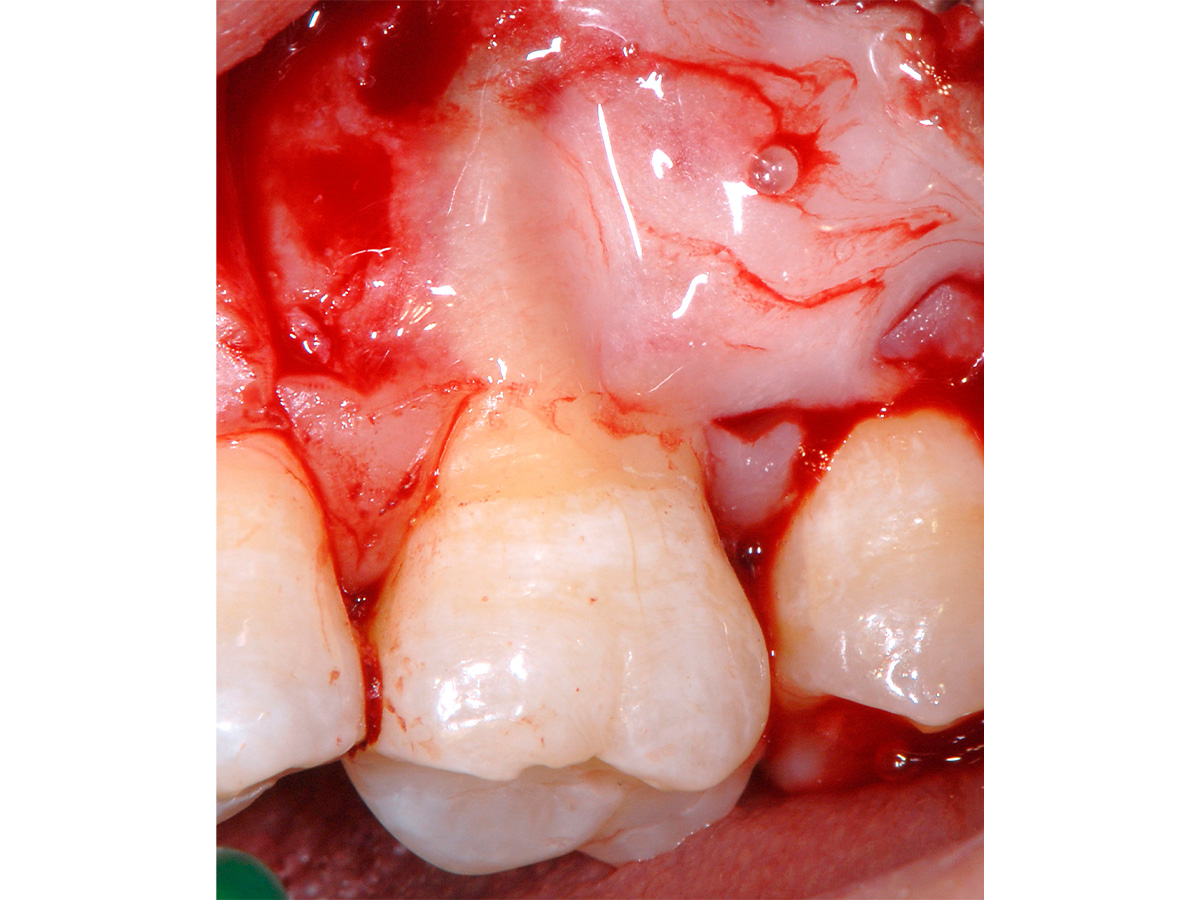

Abbildung 4

Hartgewebsbearbeitung: Bearbeitung der Wurzeloberflächen mit Hand- und Ultraschallinstrumenten im Bereich des parodontalen Defektes.